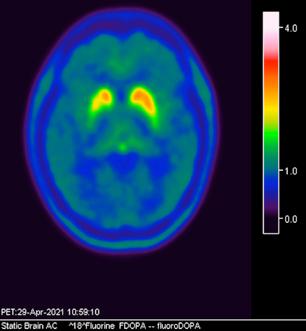

Femenino de 65 años, antecedente de hipertensión arterial de 20 años de evolución en control. Sin antecedentes familiares relevantes de enfermedades neurológicas. Acudió a consulta médica por deterioro progresivo en su capacidad motora y dificultades en las actividades diarias. Desde hace 2 años ha notado cambios en su marcha y en su habilidad para realizar movimientos finos con las manos principalmente del lado izquierdo, rigidez muscular, temblor en reposo siendo mayor del lado izquierdo y dificultad para iniciar y mantener el movimiento, especialmente al levantarse de una silla o al comenzar a caminar. Además, los familiares han observado que tiene una expresión facial inexpresiva y que su voz se ha vuelto más monótona. A la exploración física con expresión facial inexpresiva, temblor de reposo bilateral en manos de predominio izquierdo, rigidez muscular generalizada, más pronunciada en las extremidades superiores, bradicinesia evidente en la realización de movimientos finos de las manos, marcha festinante con pasos cortos y arrastrando los pies, reflejos osteotendinosos normales, no se observan déficits sensoriales. Se realiza adicionalmente la escala de Evaluación de la Enfermedad de Parkinson (UPDRS) con un total de 35 puntos, indicando moderada afectación de la enfermedad. Inicialmente se realiza una tomografía simple de cráneo, sin alteraciones estructurales, al no encontrar algún hallazgo se decide realizar posteriormente Resonancia Magnética Cerebral 1.5 Tesla: sin alteraciones estructurales significativas. Por este motivo y ante la alta sospecha clínica se realiza estudio de imagen molecular PET-RM con 6-[18F] FDOPA en equipo 3 Tesla en el cual se observa la disminución de la captación de la 6-[18F]FDOPA a nivel de putamen y caudado de predominio derecho evidenciando la degeneración dopaminérgica nigro presináptica a este nivel, con un patrón tipo 2 (Egg shaped) así como la mala definición de nigrosoma, estos hallazgos compatibles con enfermedad de parkinson. (Figura 1 y 2)

Actualmente, el diagnóstico del Parkinson se basa principalmente en métodos convencionales que incluyen: -Presencia de 2 de los 3 síntomas principales, con ausencia

axial fusionada de PET-RM 3T con

con disminución de la captación del radiotrazador a nivel de ambos putámenes en la región posterior y media de predominio derecho así como disminución en el caudado ipsilateral.

2. Reconstrucción tridimensional avanzada de imagen híbrida PET-RM 3T con 6-[18F]FDOPA observando disminución de la captación del radiotrazador a nivel de ambos putámenes en la región posterior y media así como en el núcleo caudado derecho.

Figura 3. Reconstrucción mediante imagen molecular de imagen híbrida PET-RM 3T con 6-[18F] FDOPA observando disminución de la captación del radiotrazador a nivel de ambos putámenes en la región posterior, media y anterior así como en ambos núcleos ca dados de predominio derecho.

Figura 4. Reconstrucción mediante imagen molecular de imagen híbrida PET-RM 3T con 6-[18F]FDOPA observando captación adecuada y conservada del radiotrazador en el cuerpo estriado (ambos putámenes y núcleos caudados) en un paciente negativo para enfermedad de parkinson.

En cuanto al campo de los estudios de imagen convencional y de laboratorio no existe alguna prueba que pueda confirmar la enfermedad. Sin embargo, las imágenes de diagnóstico por métodos de imagen molecular del tipo no invasivas, como la tomografía por emisión de positrones (PET) en conjunto con un resonador de 3 tesla (RM 3T), pueden respaldar el diagnóstico de un médico, actualmente éste método tiene una sensibilidad diagnóstica de 95.4%, especificidad 100%, valor predictivo positivo del 100% y valor predictivo negativo del 87.5%. (5,6)

La enfermedad de parkinson es una enfermedad neurodegenerativa con afectación principalmente motora (temblor, rigidez y acinesia) de sospecha y diagnóstico clínico, ante la limitación de los estudios de laboratorio y métodos de imagen convencional para el diagnóstico toman gran relevancia las técnicas de imagen molecular no invasivas como el PET-RM y PET-CT con 6-[18F]FDOPA que cuentan con gran sensibilidad y especificidad para respaldar o descartar el diagnóstico médico ante la sospecha de la enfermedad de parkinson y algunas otras enfermedades del trastorno del movimiento.